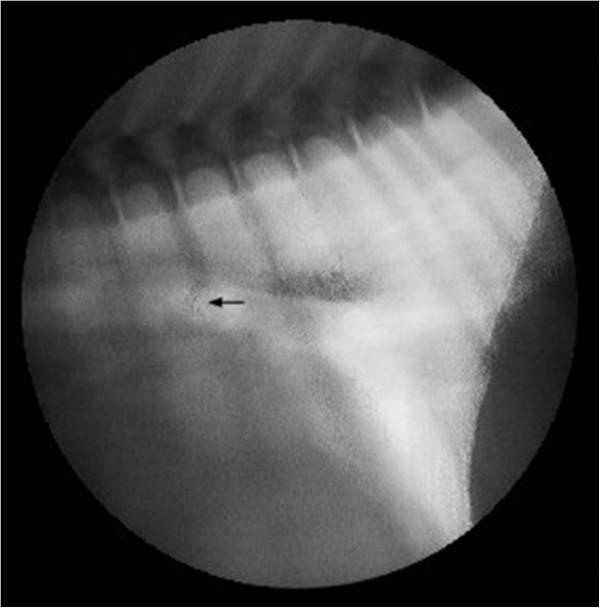

A seven-month-old intact female Spanish Water Dog was presented for further investigation of recurrent respiratory symptom. Bronchoscopy revealed a small hole-like defect in the tracheal wall at the bifurcation. The finding of the contrast material swallow study under fluoroscopy was indicative of a TEF. To further evaluate the connection between the trachea and esophagus, a computed tomography scan was performed. The TEF was surgically approached by thoracotomy through the right lateral sixth intercostal space. The fistula was identified, double ligated and divided. Histopathology confirmed the process to originate from the esophagus and to be patent. The dog was re-examined two weeks and ten months after surgery, with no evidence of recurring clinical signs.

Contrast material swallow study using fluoroscopy was the most reliable diagnostic method. Bronchoscopy may allow the fistula to be visualized, but due to a small fistular opening it can lead to a false negative result. Surgical correction by ligation and dividing of the fistula suggests a good prognosis for early diagnosed and operated TEF.